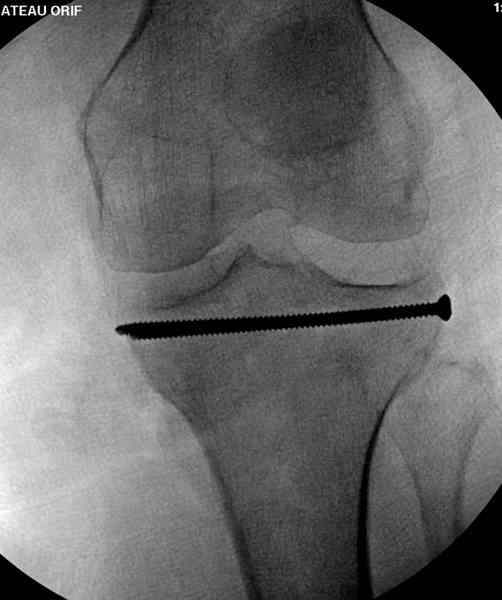

Из медиального окна можно приподнять латеральную

импрессию. Фиксация тремя параллельными шурупами в

эпифизарной части над импрессией. Создается крыша,

которая предупредит коллапс. На образовавшуюся полость - костная пластика из аутокости или синтетический заменитель. Мы применяем Osteoset в 4-5 мм диаметре таблеточки или иньекционную форму Prodens.